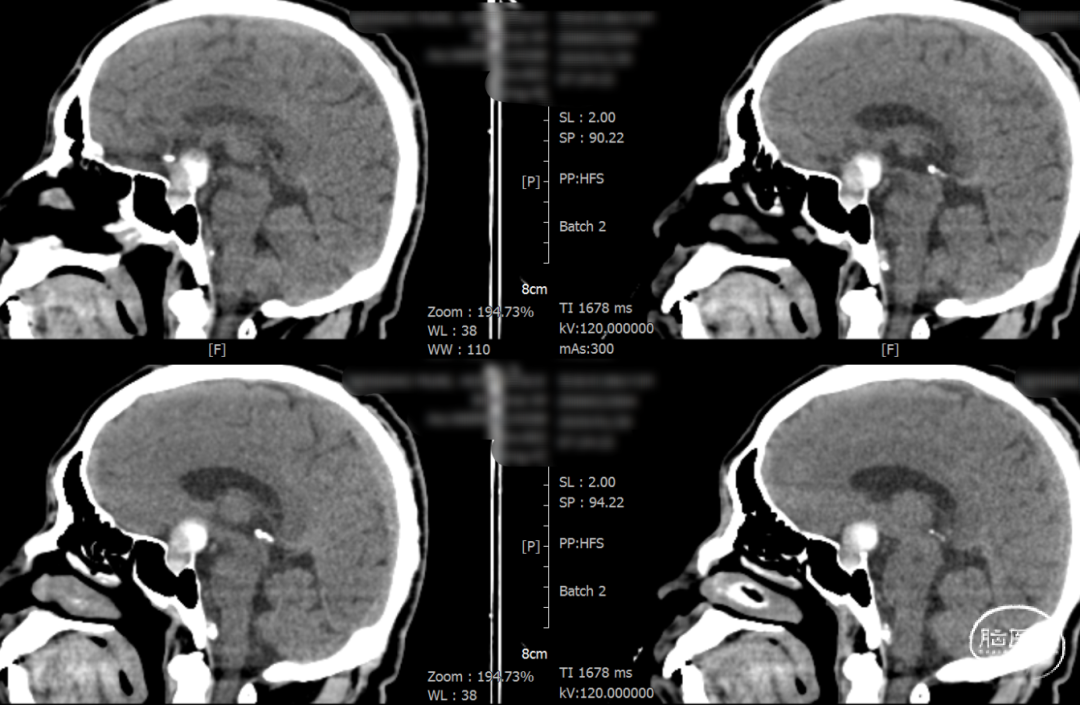

辅助检查示:2025-01-08 鞍区及垂体MR平扫:鞍内及鞍上肿瘤,垂体瘤并卒中?建议鞍区及垂体MR增强扫描。

2025-1-19 DSA造影3D重建及方案讨论:

DSA造影3D重建测量

术后一天检查。